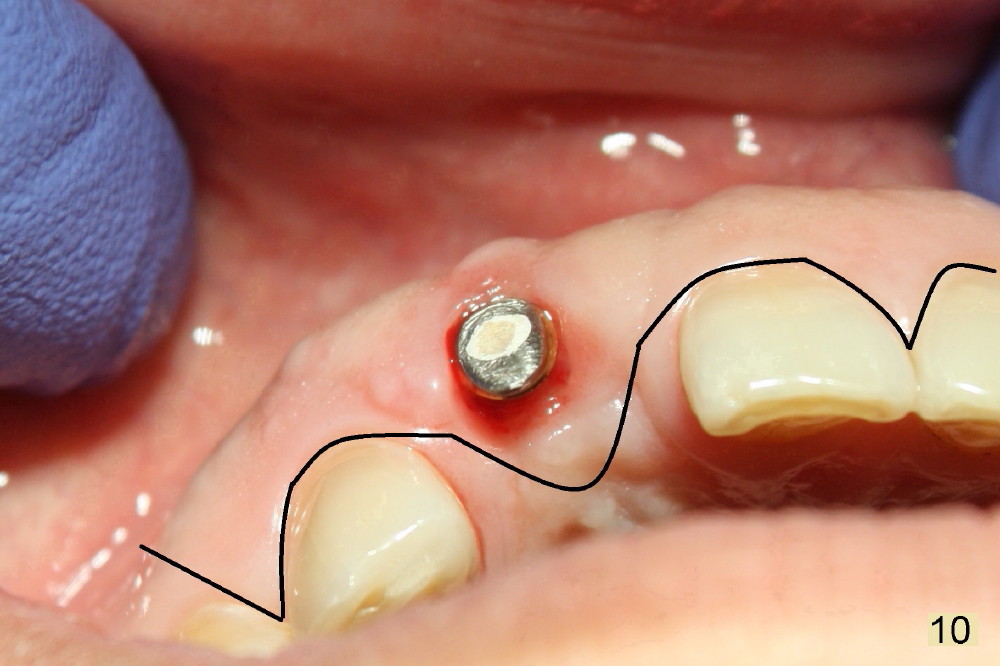

Fig.7,8 show the provisional 10 days and 1.5 months postop, respectively. When the provisional is removed, the implant/abutment is buccally malpostioned (Fig.9). It appears that segmental osteotomy is necessary. Fig.10 shows incision design. The implant and bone complex is to be moved to an ideal position (Fig.11,12). A block graft is inserted apically for internal fixation. An ortho wire is used for external fixation.